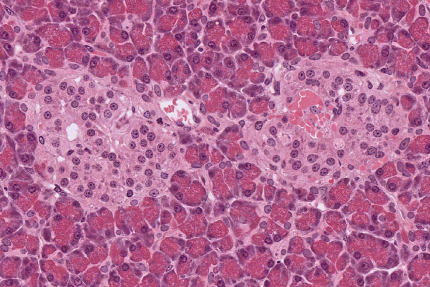

Le pancréas est constitué de cellules acineuses pancréatiques, qui apparaissent foncées. Elles sont impliquées dans la fonction exocrine du pancréas : la sécrétion d'enzymes digestives. Au centre de l'image, deux îlots de Langerhans apparaissent plus clairs. Ces îlots remplissent la fonction endocrine du pancréas avec notamment la sécrétion d'insuline par les cellules β et de glucagon par les cellules α. Observation en microscopie optique, coloration hématoxyline-éosine. Source : collection de l'université du Mississippi.

L’insuline est sécrétée par les cellules β des îlots de Langerhans du pancréas (Figure 2). Elle a un rôle majeur dans le maintien de l’homéostasie glucidique par ses actions qui facilitent, d’une part, l’utilisation et le stockage du glucose, et d’autre part l’inhibition des mécanismes susceptibles de faire augmenter sa concentration plasmatique.